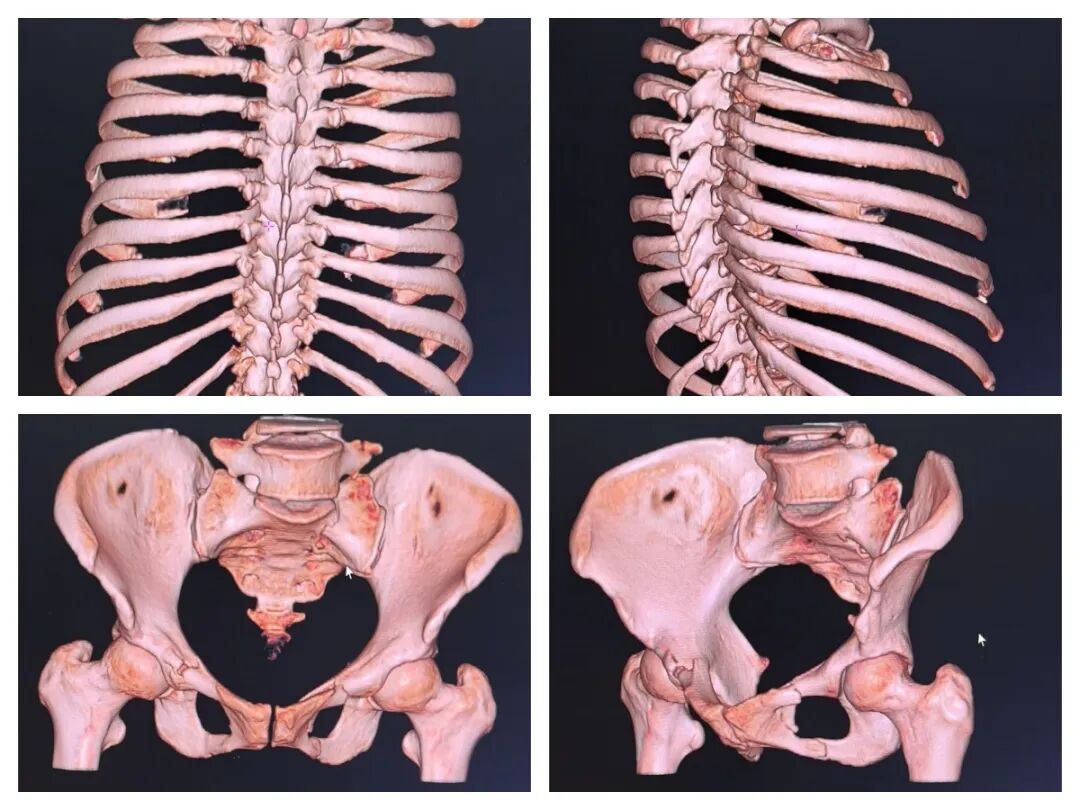

联影ct怎么样杞县中心医院影像诊断“利器”——联影高端螺旋CT_https://www.jmylbn.com_新闻资讯_第2张

△骨骼三维成像